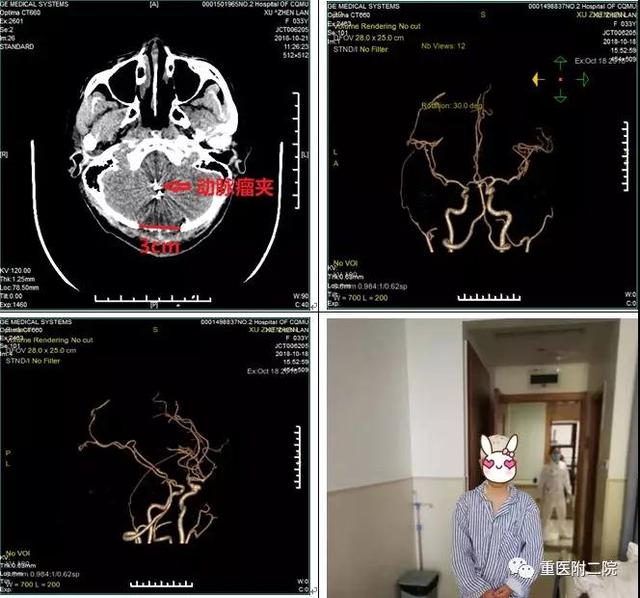

程远教授决定为患者实施枕下后正中锁孔入路小脑后下动脉瘤夹闭术。经过约3小时的全麻手术,术后患者很快苏醒,四肢运动良好。

复查CT颅内脑组织无出血、梗塞,CTA显示动脉瘤夹闭完全,载瘤动脉保留完好,无明显的血管痉挛。一周后拆线出院,家属及患者深感满意。待患者身体恢复后再次入院处理未破裂的动脉瘤。